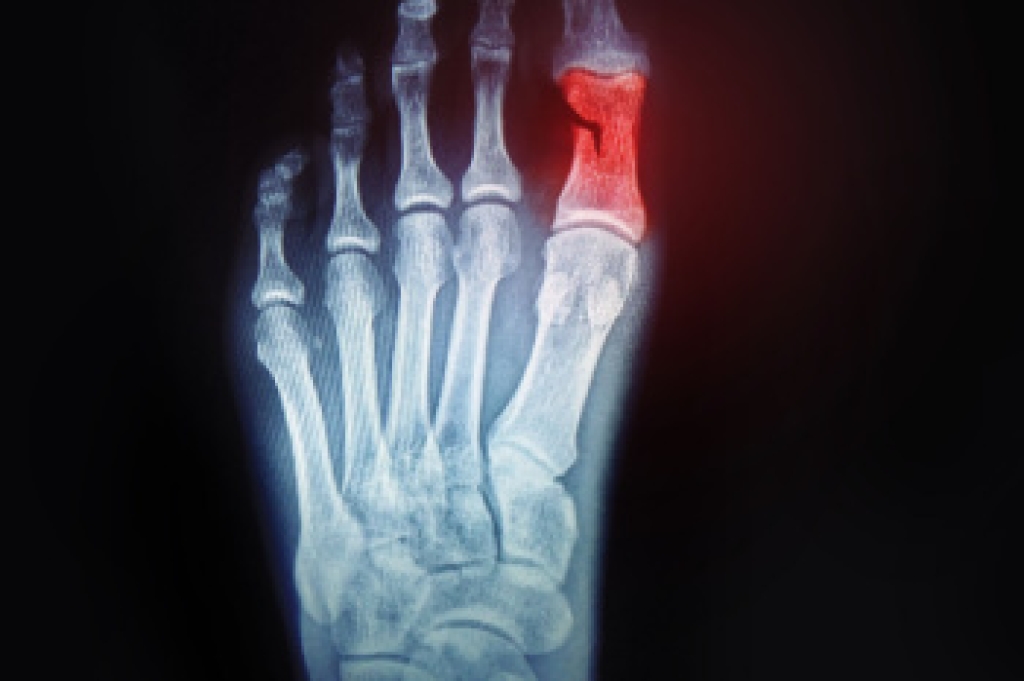

Swollen feet and ankles can result from a number of underlying causes. Often, the swelling arises when fluid accumulates in the tissues of the lower extremities, a condition called peripheral edema. Other triggers include injuries like sprains or fractures, which can lead to localized swelling in one foot or ankle. Kidney issues can impair the body's ability to eliminate excess fluid, which may result in swelling of the feet. Similarly, heart problems often lead to poor circulation, with fluid pooling in the feet and ankles, especially later in the day. Venous insufficiency, where veins struggle to return blood from the legs to the heart, can also lead to this problem. Infections, such as cellulitis, may cause sudden swelling, warmth, and redness. A podiatrist can identify the cause of swelling and provide appropriate treatment options, including compression therapy, guidance on managing chronic conditions, and preventive measures for injury-related swelling. If you have swollen feet or ankles, it is suggested that you make an appointment with a podiatrist for treatment.